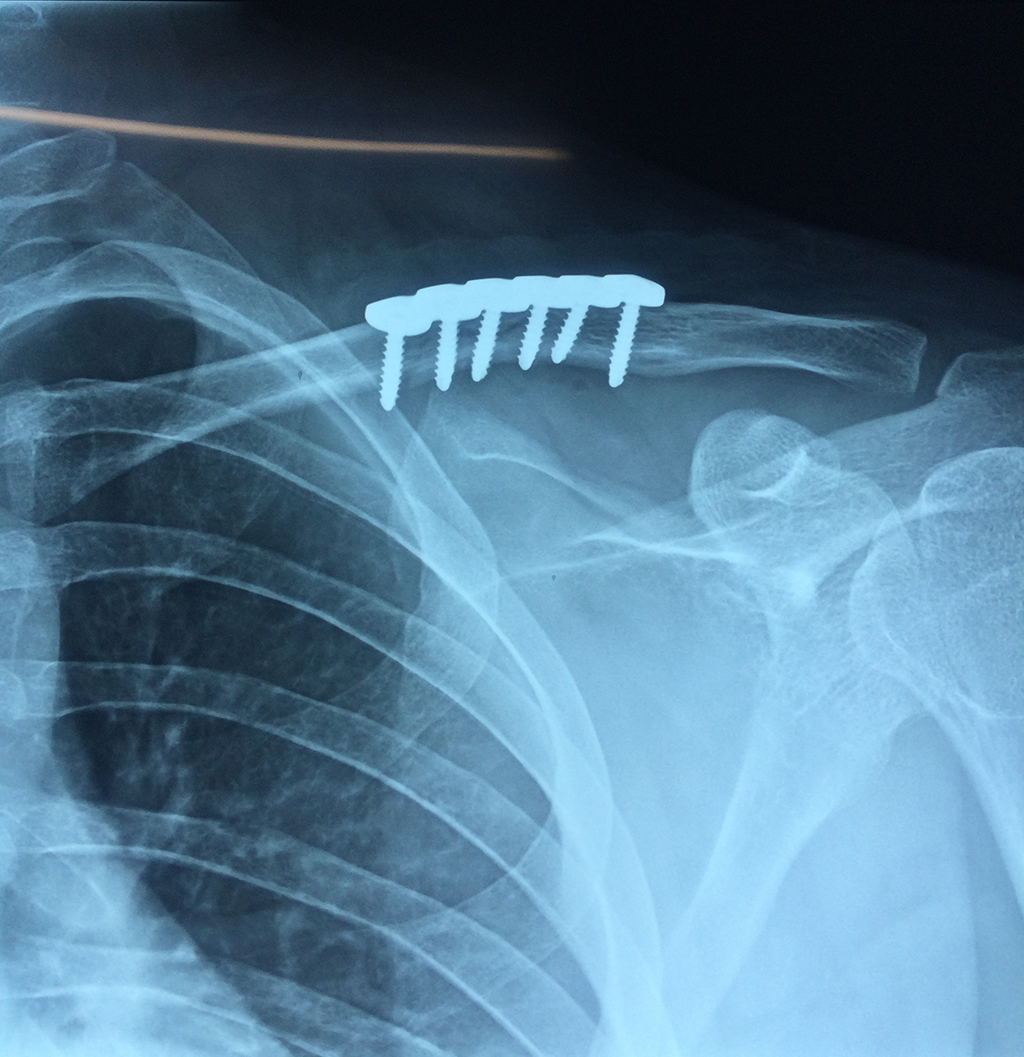

Húmero - Clavícula

La clavícula es un hueso largo, con forma de "S" itálica, situado en la parte anterosuperior del tórax. Junto con la escápula forman la cintura escapular. Se puede palpar por toda su longitud y se extiende del esternón al acromion de la escápula, siguiendo una dirección oblicua lateral y posterior.

Se considera el único medio de unión entre el miembro superior y el tórax. A pesar de su aspecto, similar al de un hueso largo, posee una estructura semejante a la de un hueso plano, ya que carece de epífisis y de diáfisis, lo que la harían entrar dentro de la clasificación de hueso largo. Carece de un canal medular propiamente dicho.